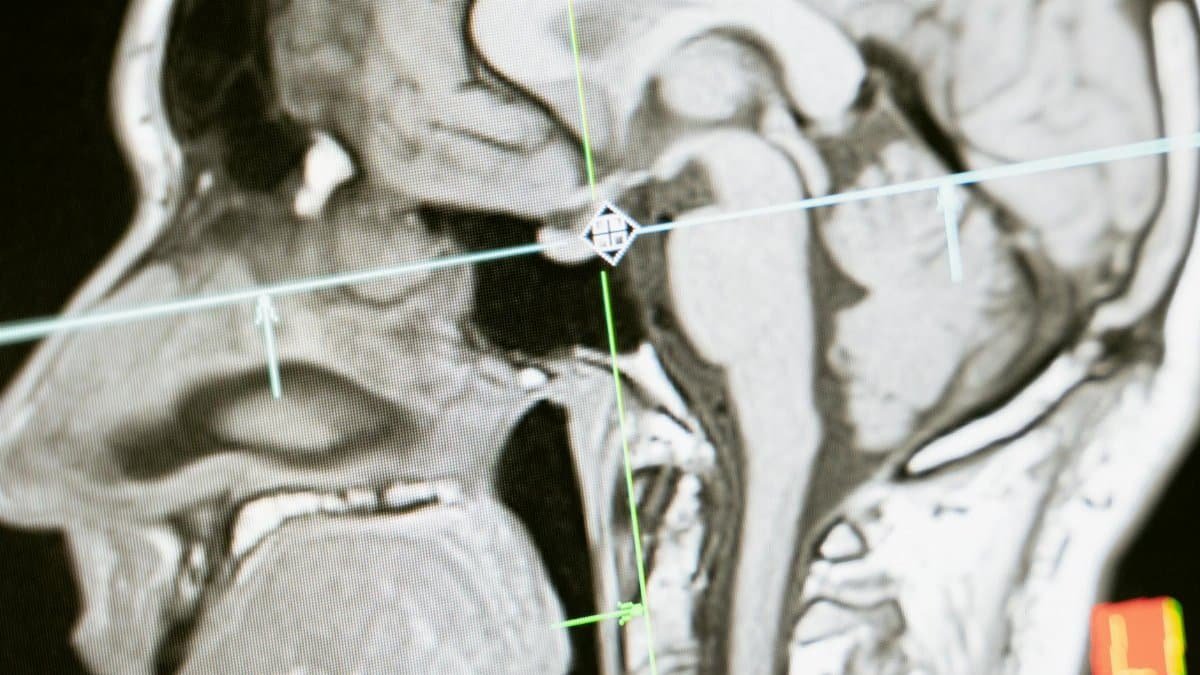

For decades, coffee has been more than a morning ritual; its become a cultural staple, with Americans brewing over 400 million cups daily. Now, a sweeping 20-year study published in Nature offers compelling evidence that this habit may safeguard the brain against some of its most feared foes. Researchers tracked more than 365,000 participants across Britain and found that those consuming two to three cups a day faced a 16 to 21 percent lower risk of dementia and a 27 to 30 percent reduced chance of Parkinsons disease compared to non-drinkers. This finding spotlights coffee brain health benefits in a fresh light, suggesting your daily joe could be a quiet ally in preserving mental sharpness as we age.

The research, detailed in a recent Nature article (read it here), stands out for its scale and duration. Beginning in 2006, scientists from the UK Biobank analyzed genetic data, lifestyle factors, and health records from a diverse cohort. What emerged was a dose-dependent pattern: moderate coffee intake correlated with fewer neurodegenerative incidents, even after adjusting for smoking, exercise, and diet. Lead author Sara Imarisio noted in interviews that the studys rigor minimizes confounding variables, making it one of the strongest links yet between habitual coffee consumption and brain resilience.

This isnt anecdotal; its derived from incident cases verified through hospital records and death registries. For context, dementia affects over 55 million people worldwide, with Parkinsons impacting 10 million. If replicated, these results could influence public health recommendations, much like past studies elevated the status of Mediterranean diets.

A 2022 review in Nutrients (link) corroborated this, showing how these compounds reduce inflammation in microglial cells, the brains immune responders. In animal models, coffee extracts have reversed amyloid plaque buildup, a hallmark of Alzheimers. Human trials lag, but the UK Biobank data bridges that gap with real-world proof.

Caffeine alone merits a spotlight. Epidemiological data from the Honolulu-Asia Aging Study, spanning 1980 to 1997, linked higher intake to delayed Parkinsons onset by up to 10 years in men (source). It fosters neurogenesis in the hippocampus, the memory center, while enhancing blood flow to gray matter.